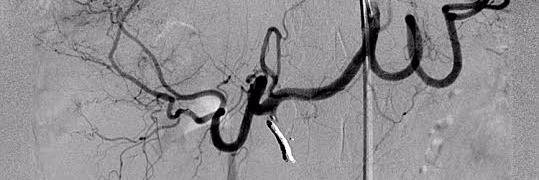

Did a great endoleak case today @AlbanyIR with @gsiskin...enlarging sac with new type II leak on CTA. Coil embolized the outflow lumbar artery and filled the space with EVOH! Excellent education on the principles of different embolics and when to use them!